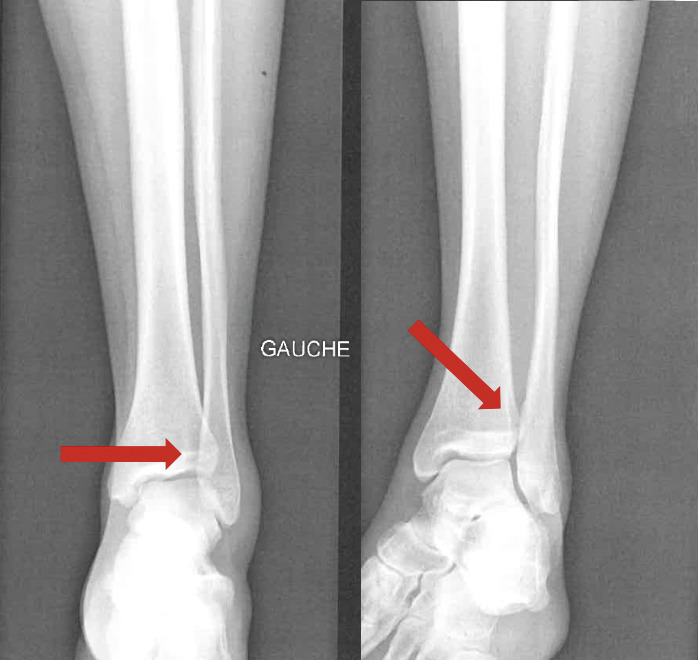

Une IRM confirme l’entorse grave dite « de la syndesmose », avec rupture complète du ligament tibiofibulaire antéro-inférieur (LTFAI) et de la membrane interosseuse (fig. 2 et 3 ), mais le ligament tibiofibulaire postéro-inférieur (LTFPI) est intact. L’absence de diastasis tibiofibulaire au bilan radiologique complémentaire classe la lésion en stade 2 (fig. 4).

En cas de suspicion clinique, les radiographies initiales de face et de profil, en charge, permettent de classer la lésion en cherchant un diastasis tibiofibulaire dont les critères d’interprétation sont les suivants :

– espace clair médial (normal inférieur à 4 mm) ;

– espace clair tibiofibulaire (normal entre 3 et 6 mm sur un cliché de face) ;

– superposition tibiofibulaire (normale supérieure à 5 mm sur un cliché de face stricte, ou supérieur à 1 mm sur un cliché en rotation interne de 20 ° [incidence de mortaise]).2

En cas de doute, le cliché comparatif controlatéral peut aider.

Des clichés de profil sont également nécessaires pour éliminer une fracture de la malléole postérieure du tibia, fréquemment associée à ce type de traumatisme.